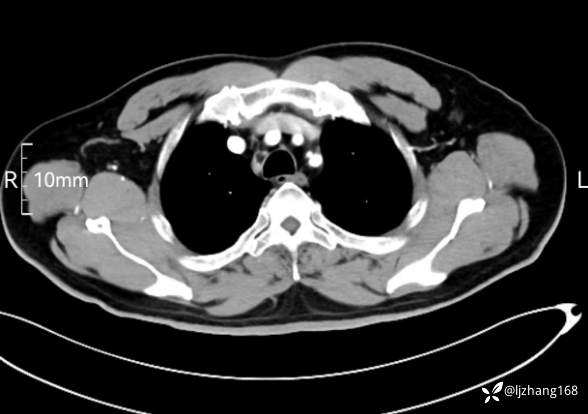

辅助检查:糖化血红蛋白12.3%。肺炎支原体IgG、IgM、呼吸道合胞病毒均未见明显异常。胸部CT:右肺上叶阻塞性肺炎。